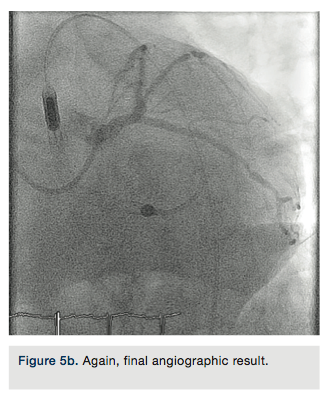

LAD guide wire was withdrawn and the LAD was rewired through the LM portion of the stent. A 3.5 x 15mm Sprinter balloon (Medtronic) was used to cross into the LAD and inflated at 18atm. A 3.5 x 12mm Resolute Integrity stent was deployed at the proximal LAD into the LM at 18atm. The LCX guide wire was pulled back into the guide catheter, and re-advanced into the LCX through the LM stent. Two 3.5 x 15mm NC Sprinter balloons were placed from the LM to the LCX and LAD, and a simultaneous “kissing” inflation was performed at 14atm (Figure 4). A 4.0 x 12mm NC Sprinter balloon was inflated in the LM portion of the stents at 18atm for proximal optimization. IVUS examination revealed excellent stent apposition (Figures 5a-5b). The stenoses in the proximal, mid and distal LAD were not treated. All catheters were removed except the Impella catheter, which was anchored in place using sutures.